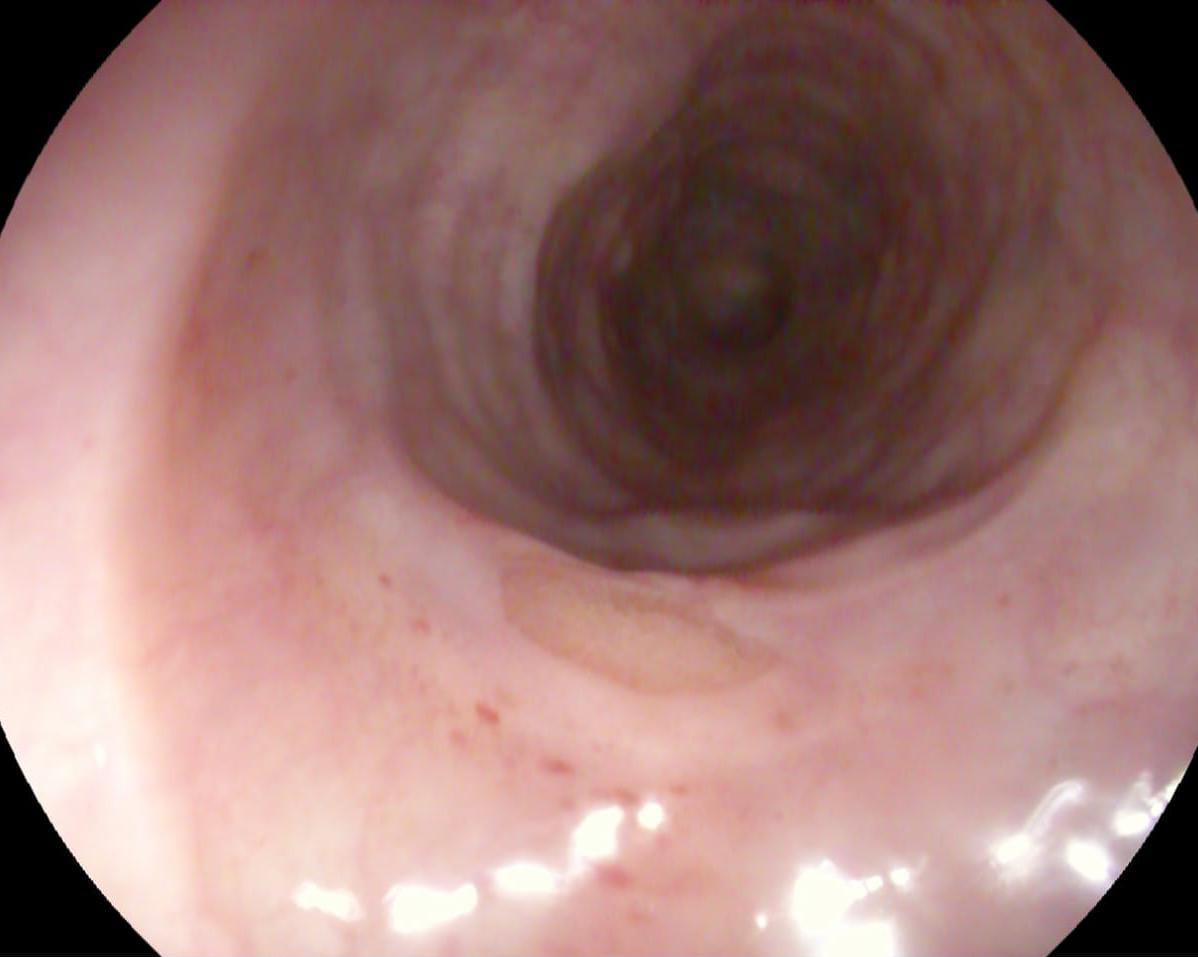

على الفور تم استدعاء فريق طوارئ المناظير، وتم عمل منظار معدة تشخيصي طوارئ حيث تم تفتيت قطعة اللحم واستخراج العظمة وأجزاء من قطعة اللحمة، وتحريك المتبقي لتجويف المعدة، وإزاحة الانسداد، كما تم عمل منظار تشخيصي كامل للحالة حتى الإثنى عشر، وبعد الانتهاء من الفحص تبين وجود تحور في نسيج المرئ العلوي، وتم أخذ عينات وإرسالها للتحليل الباثولوجي، وخروج المريض بسلام بعد كتابة العلاج والإرشادات اللازمة له.